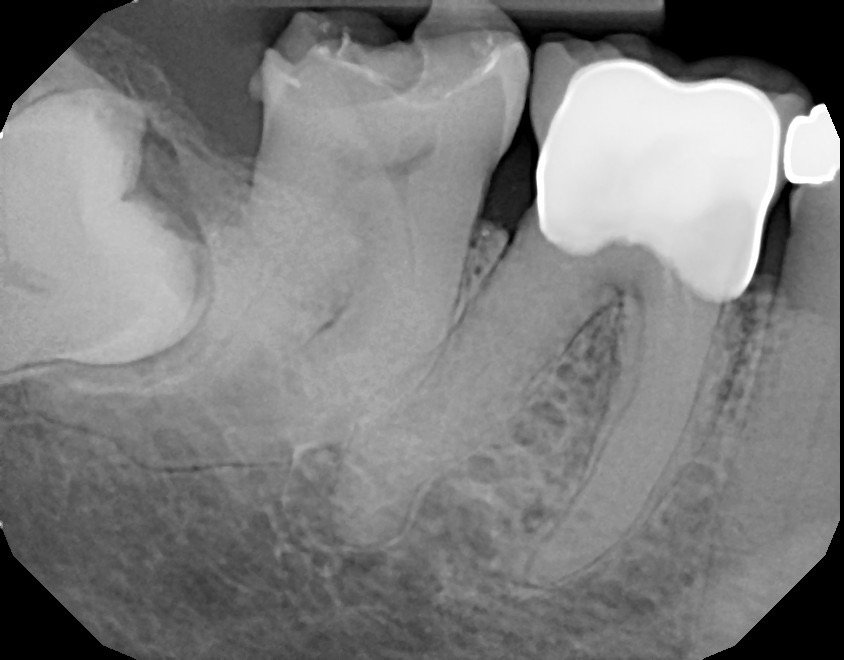

Tooth #31 with a very curved and calcified root canal system with limited access.